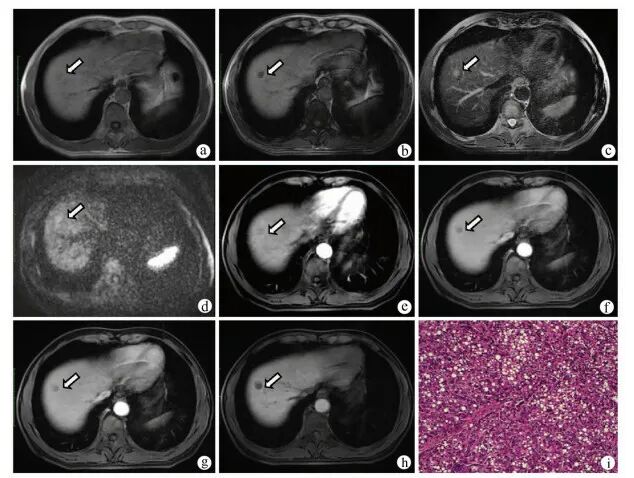

图3 患者男,57岁,肝硬化12年,肝脏S6段结节注:a,病灶同相位呈稍高信号(箭头);b,反相位未见信号减低(箭头);c,T2WI呈稍高信号(箭头);d,DWI呈高信号(箭头);e,增强扫描动脉晚期轻度强化(箭头);f,门静脉期呈稍高信号,持续强化(箭头);g,延迟期强化减低,呈低信号(箭头);h,肝胆期呈低信号;i,病理学诊断为高分化HCC(HE染色,×100)。

3.2.1 T1WI eHCC主要呈等信号,可呈稍低信号,仅极少数表现为高信号;部分结节反相位信号减低,提示其内存在脂肪变性。

3.2.2 T2WI eHCC主要呈等或稍高信号,仅极少数表现为低或混杂信号。

3.2.3 DWI eHCC多表现为DWI高或稍高信号,ADC图呈低信号,提示病灶水分子弥散受限。

3.2.4 动态增强 eHCC多表现为动脉期(动脉晚期)等信号、少数为稍高信号,极少数表现为低信号;门静脉期及延迟期呈等或低信号,尚未见呈高信号的报道。

3.2.5 肝细胞特异性对比剂对比增强MR eHCC于肝胆期多呈低信号。